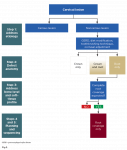

The first step in sequencing in the RSC algorithm is to manage the etiology (Figure 1). This can be done through medical consultation, diet modification, oral hygiene instruction, modification of toothbrushing technique, and occlusal adjustment as needed. Once a plan for management of etiologic agents has been discussed, replacement of hard and soft tissues may be attempted.

The next step involves identifying the extent of the lesion (Figure 1). This can be done by locating the cementoenamel junction (CEJ) of the tooth. In cases where the CEJ is not clinically discernable, an estimation based on knowledge of anatomic measurements of teeth may be used. Once the CEJ is identified, the lesion is categorized into "crown only," "root only," and "combination defect." The crown-only cervical lesion is limited to anatomic crowns, involves enamel and/or coronal dentin of the tooth, and is located coronal to the CEJ. The root-only cervical lesion involves cementum and/or radicular dentin and is located apical to the CEJ. The combination defect extends across the CEJ involving both the crown and exposed root and affecting enamel, cementum, and/or dentin. For carious teeth, the anticipated defect dimension after caries removal must be used to classify the sites as crown-only, root-only, or combination.

In this step an evaluation is made of the clinical examination of the soft tissue, radiographic bone level, and prediction of the amount of root coverage expected (Figure 1). The soft-tissue evaluation includes assessment of gingival phenotype, amount of keratinized tissue width, and depth of vestibule. Sites with thick phenotype and more that 2 mm of keratinized tissue width have shown to have better health indicators, esthetics, and patient comfort.26 Conversely, for sites with thin phenotype and inadequate keratinized tissue width, phenotype enhancement through soft-tissue grafting may be considered to improve periodontal stability, especially in cases of restorations.26 Thus soft-tissue evaluation is important to determine if grafting is necessary. For prediction of root coverage, absence of interdental bone loss with complete papillae fill is a good indicator for obtaining complete root coverage in root-only cervical defects.27-29 Conversely, if there is interdental bone and papillae loss, the predictability for complete root coverage is reduced.27-29 Thus, identifying the interdental bone level and papillae fill is important in estimating the level of root coverage to be gained with a CTG.

Once the assessment of the extent of the cervical lesion and evaluation of soft-tissue anatomy and predictability of root coverage is complete, a suitable treatment plan is selected (Figure 1). Crown-only cervical lesions that involve enamel and/or coronal dentin may be treated with restorative therapy only. A soft-tissue graft may be indicated at such sites first, if the site has a thin phenotype, inadequate keratinized tissue width, and shallow vestibule to achieve a more predictable outcome in the long-term. For lesions limited to the root surface (cementum and/or root dentin), which are commonly associated with gingival recession, only mucogingival surgical procedures may be indicated, provided there is no loss of interdental bone and predictability for complete root coverage is high. However, in cases where there is loss of interdental bone, complete root coverage is not possible.27-29 Such defects are treated as a combined crown and root defect and would need restorative and surgical treatment. When the cervical lesions include both crown and root there is loss of enamel, cementum, and/or dentin. The ideal treatment of such a lesion should involve a combined restorative and surgical approach.

For lesions needing both restorative and surgical correction, a surgical approach should be attempted first, and the restoration may be completed after complete healing has occurred (Figure 1). The objective of the surgery is to position the gingival margin as close to the CEJ as possible. There has been some debate about whether restorative procedures should be done before surgical procedures for NCCLs.4 However, surgical outcomes are dependent on multiple factors and more difficult to predict than restorative outcomes. By performing surgery first, the final result becomes more predictable because the restoration can be adjusted to treat the coronal portion of the lesion and parts of the radicular portion that did not achieve coverage. If the restoration is attempted first and the surgical outcome does not achieve the desired root coverage, the restoration might have to be redone. Further, the use of a CTG increases the soft-tissue thickness and the zone of keratinized tissue. Such a thick gingival phenotype is more favorable to resist inadvertent trauma potentially caused by placement of rubber dam clamps, use of high-speed burs along the margins during tooth preparation and polishing of the restoration, and packing retraction cords during restorative treatment. Conversely, restorative therapy before mucogingival surgery may offer advantages such as better access and visibility and greater control over the emergence profile,4 but the risks outweigh the benefits.